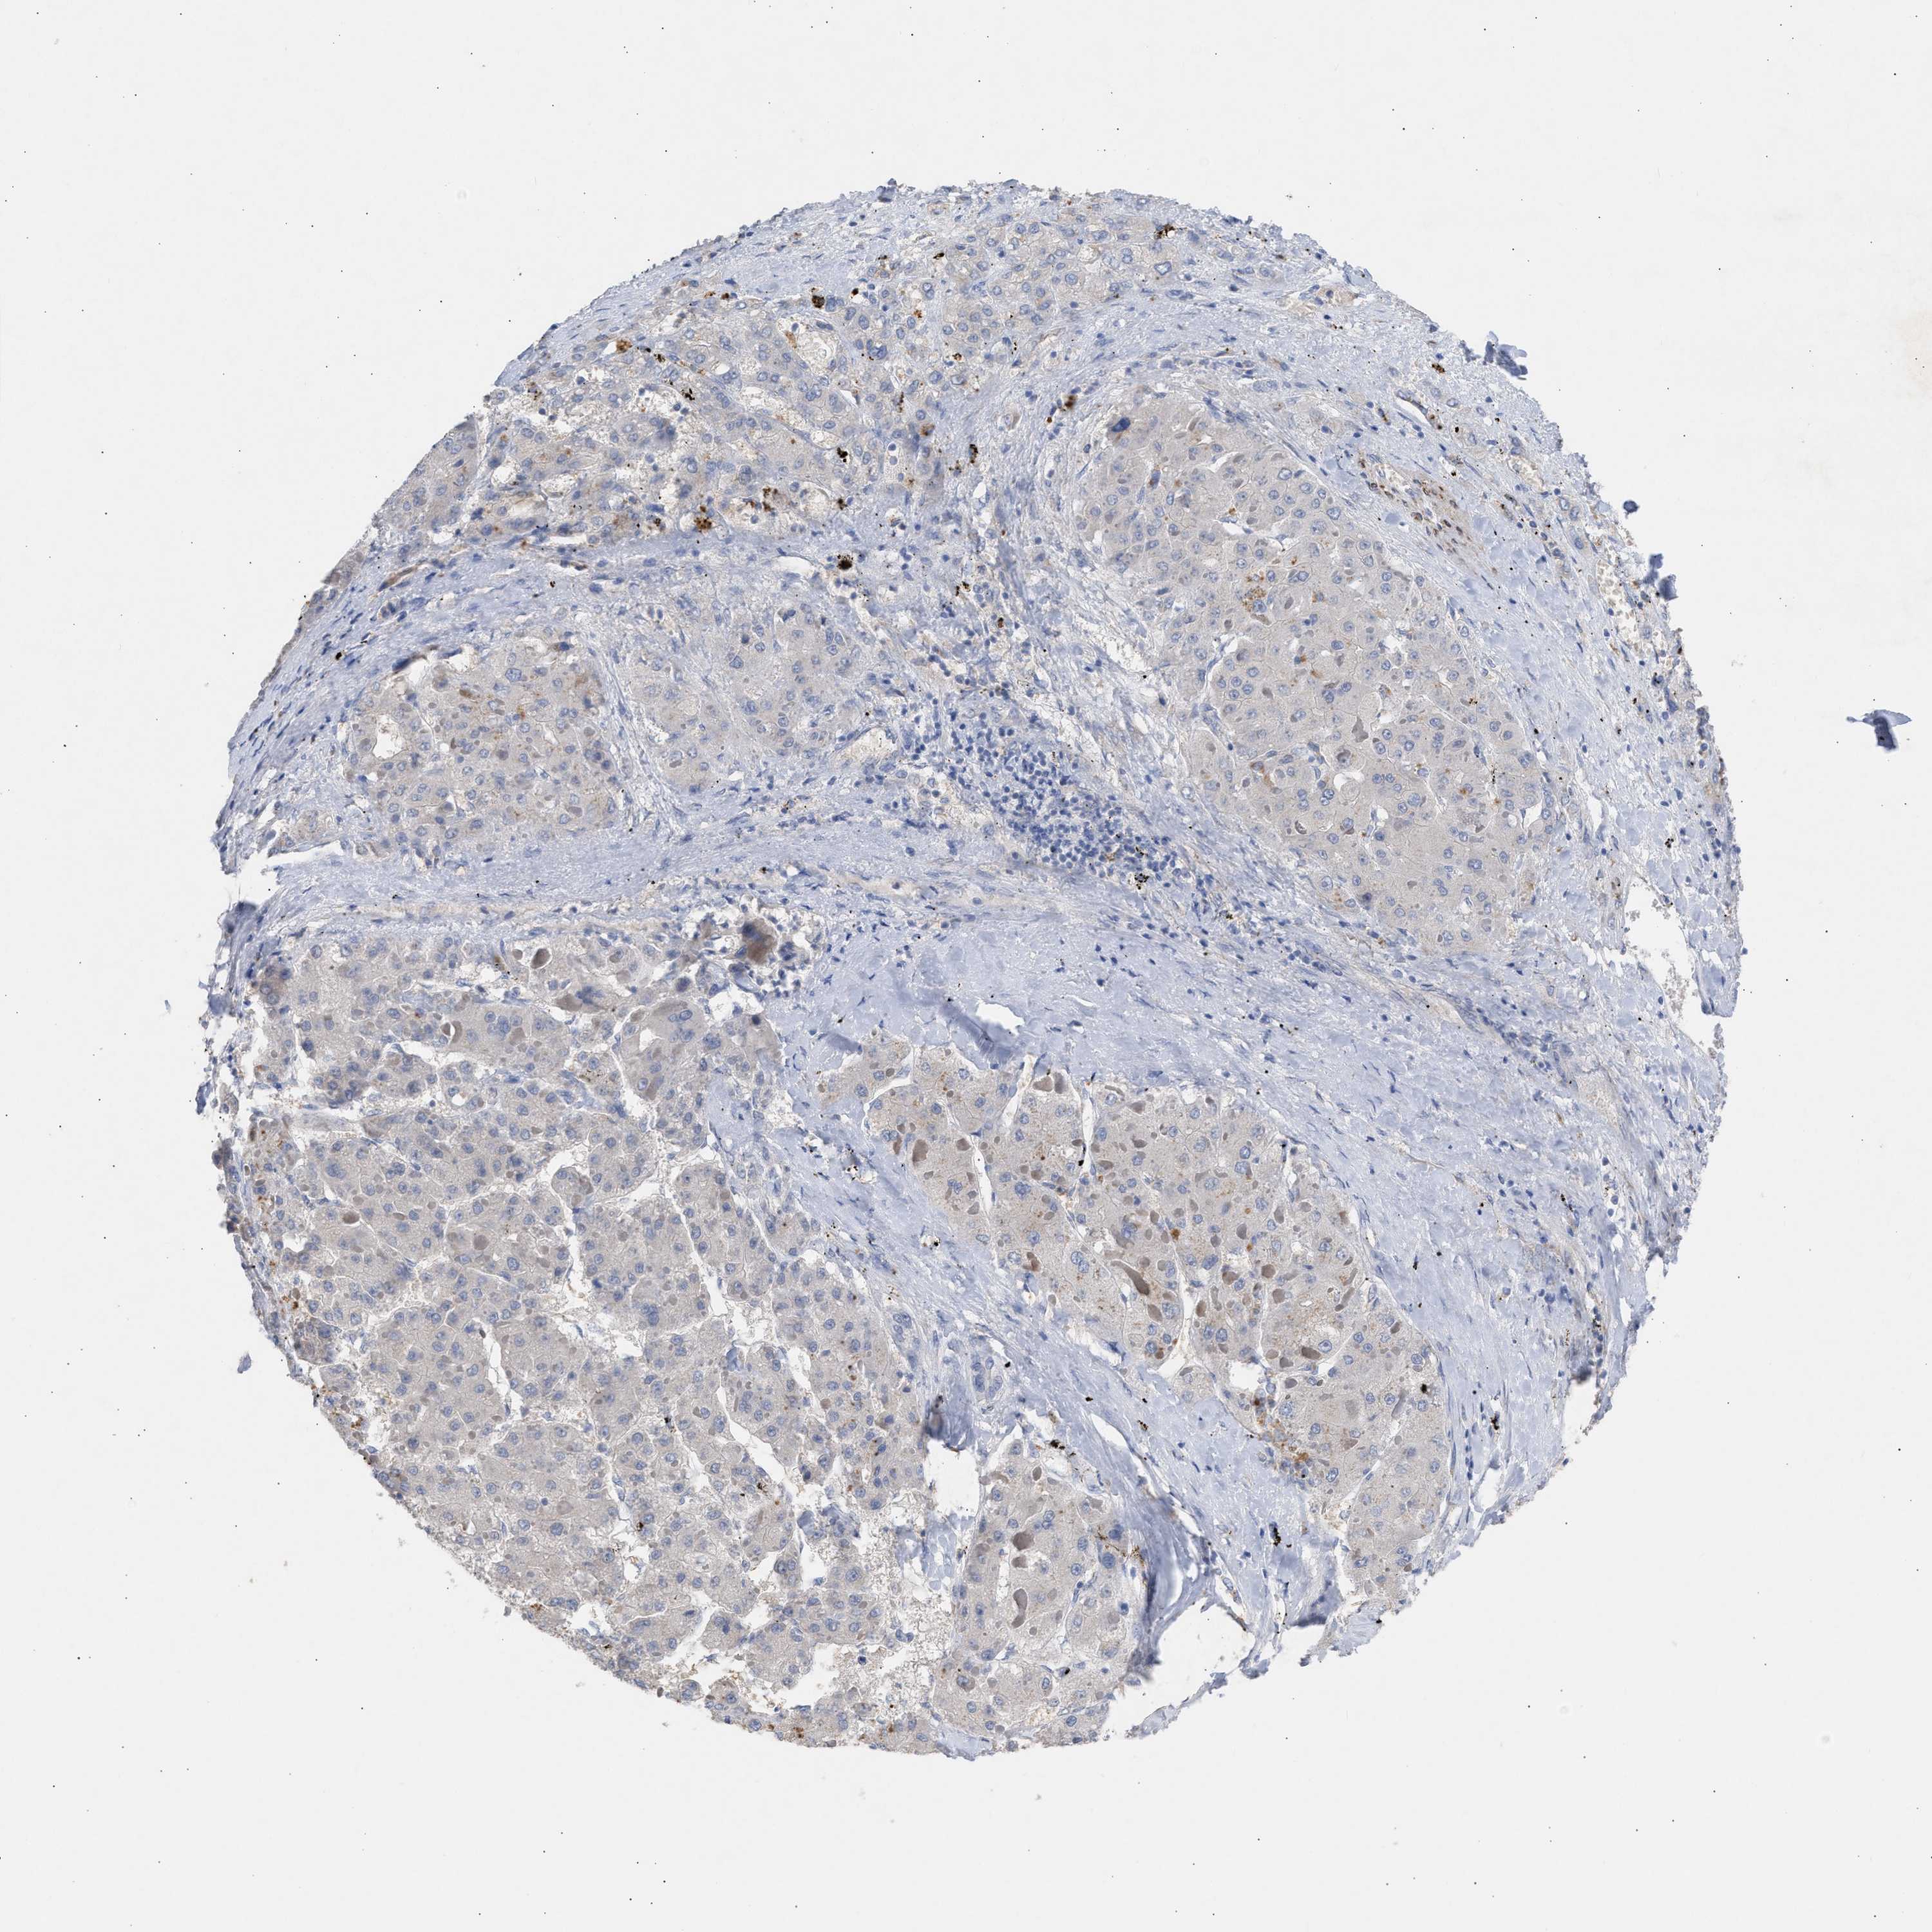

LIVER CANCER - Protein expressioni

A mouse-over function shows sample information and annotation data. Click on an image to view it in a full screen mode. Samples can be filtered based on level of antibody staining by selecting one or several of the following categories: high, medium, low and not detected. The assay and annotation is described here.

Note that samples used for immunohistochemistry by the Human Protein Atlas do not correspond to samples in the TCGA dataset.

Antibody stainingi

Antibody staining in the annotated cell types in the current human tissue is reported as not detected, low, medium, or high, based on conventional immunohistochemistry profiling in selected tissues. This score is based on the combination of the staining intensity and fraction of stained cells.

Each image is clickable and will lead to virtual microscopy that enables deeper exploration of all samples and also displays staining intensity scores, fraction scores and subcellular localization as well as patient and tissue information for each sample.

Antibody HPA019601

Antibody CAB008667

Staining

High

Medium

Low

Not detected

Intensity

Strong

Moderate

Weak

Negative

Quantity

>75%

75%-25%

<25%

None

Location

Nuclear

Cytoplasmic/membranous

Cytoplasmic/membranous,nuclear

Carcinoma, Hepatocellular, NOS

Cholangiocarcinoma